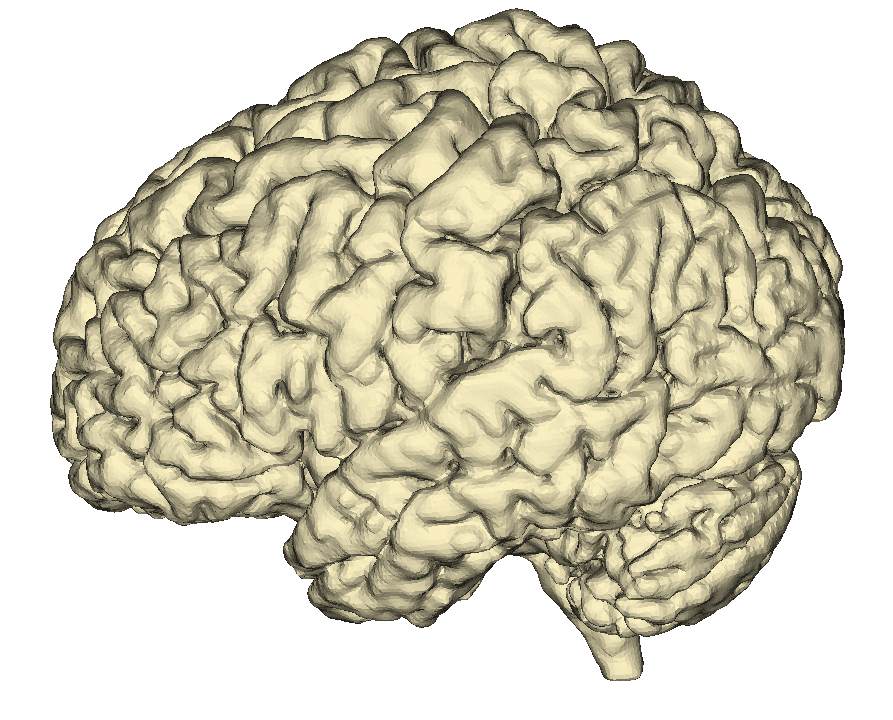

User-friendly interface with precise editing capabilities for bones, vasculature, and soft tissues. Rapidly create patient-specific anatomical models.

Segment bones, vasculature, and soft tissues with precision. User-friendly tools for accurate anatomical boundary delineation.

Real-time 3D rendering of segmented structures. Create patient-specific anatomical models for visualization and analysis.

Quickly visualize and analyze anatomical structures from CT and MRI scans. Identify abnormalities with precise 3D visualization.